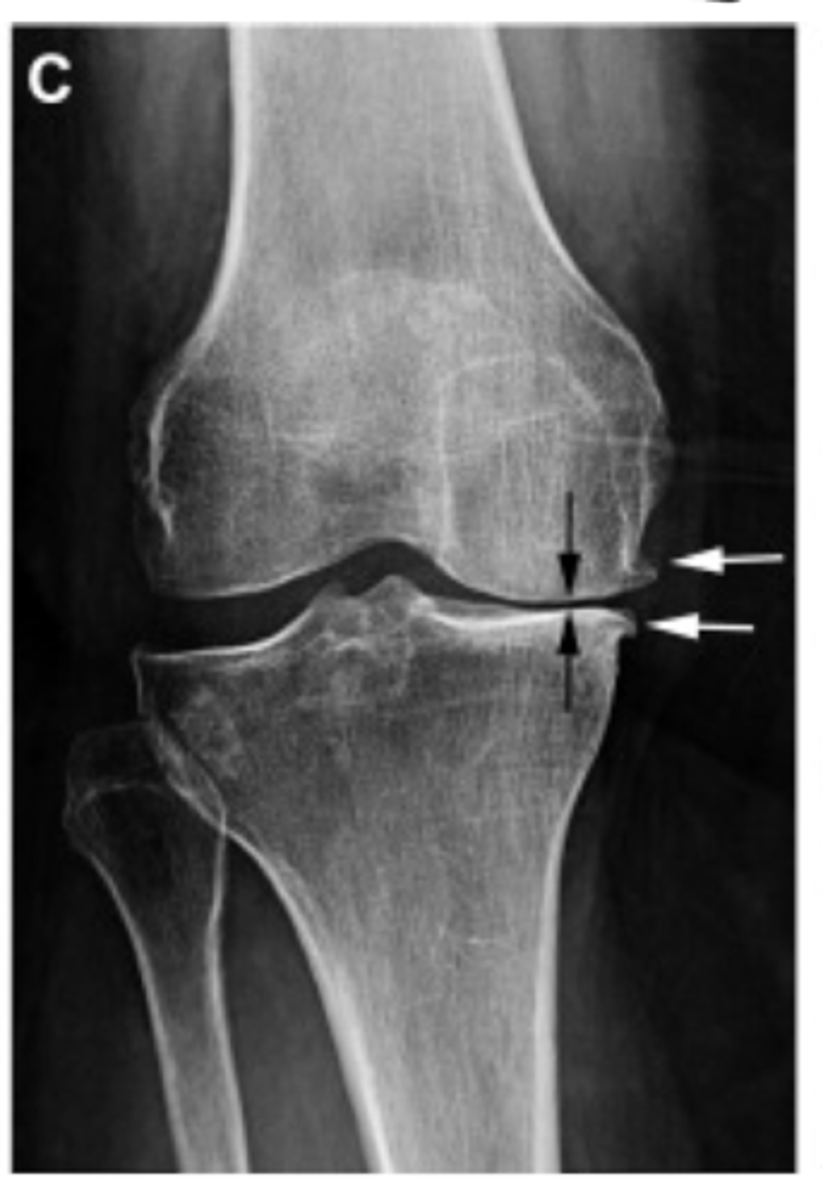

Grade I = minimal osteophytes w/ no problems w/ space or cartilage

Define the Kelgren Lawrence grade. How do you know?

Grade II = 1 definite osteophyte w/ NO space narrowing

Grade III = marginal osteophytes w/ space narrowing + sclerosis & multiple osteophytes

Grade IV = obliteration of joint space (bone on bone)